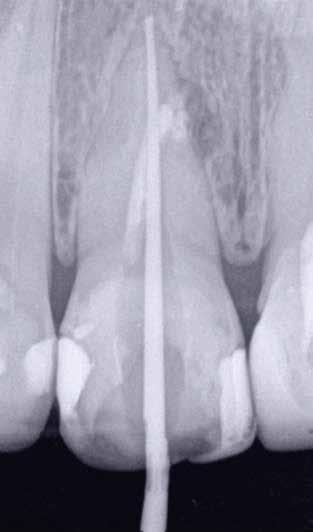

5. a–l. ábrák: Az incisális élen keresztül kialakított hozzáférés lehetővé teszi a pericervikális dentin megőrzését. Kalcifikáció esetén CBCT-felvétel készítése hasznosnak bizonyulhat a hozzáférési nyílás tervezése során (a–d) . Minden fog koronai helyreállítása a gyökértömés elkészítésével egyidejűleg történt. A négyéves (e–h) és a kétéves (i–l) kontrollok alkalmával készített röntgenfelvételeken teljes gyógyulás látható. Mindkét fog tünetmentes és funkcióképes volt. (Dr. Viraj Vora esetei)

9. a–j. ábrák: A szuvas lézión és a meglévő restaurátumon keresztül történő mezializált és distalizált hozzáférés (a–f). A fogak restaurálása közvetlenül a gyökértömések elkészítése után történt. Az egyéves kontroll során készített röntgenfelvételen a gyógyulás jelei láthatóak, annak ellenére, hogy a gyökércsatornák feltágítása konzervatív módon történt, és a pulpakamra tetejének több mint fele megőrzésre került (g–j). (Dr. Viraj Vora esetei)

zésére. Ez azért fontos, mert a frontfogak funkcionális megterhelése során – a PCD-nek megfelelően elhelyezkedő területben – jelentős stressz ébred (5. a–l ábrák) 24 Szükség esetén egy CBCT-felvételt is készíthetünk. A 3D-s adatok jelentős mértékben segíthetik a klinikus munkáját a gyökércsatorna koronális vetületének vizualizálásában, és ennek alapján az egyenes vonalú hozzáférés biztosításához szükséges belépési pont meghatározásában (5.

a–l ábrák) . Ha a kofferdám izolálás a szomszédos fogakra is kiterjesztésre kerül, úgy a kezelést végző orvos sokkal magabiztosabban tudja a gyökerek angulációját vizualizálni (3. a-b ábrák)